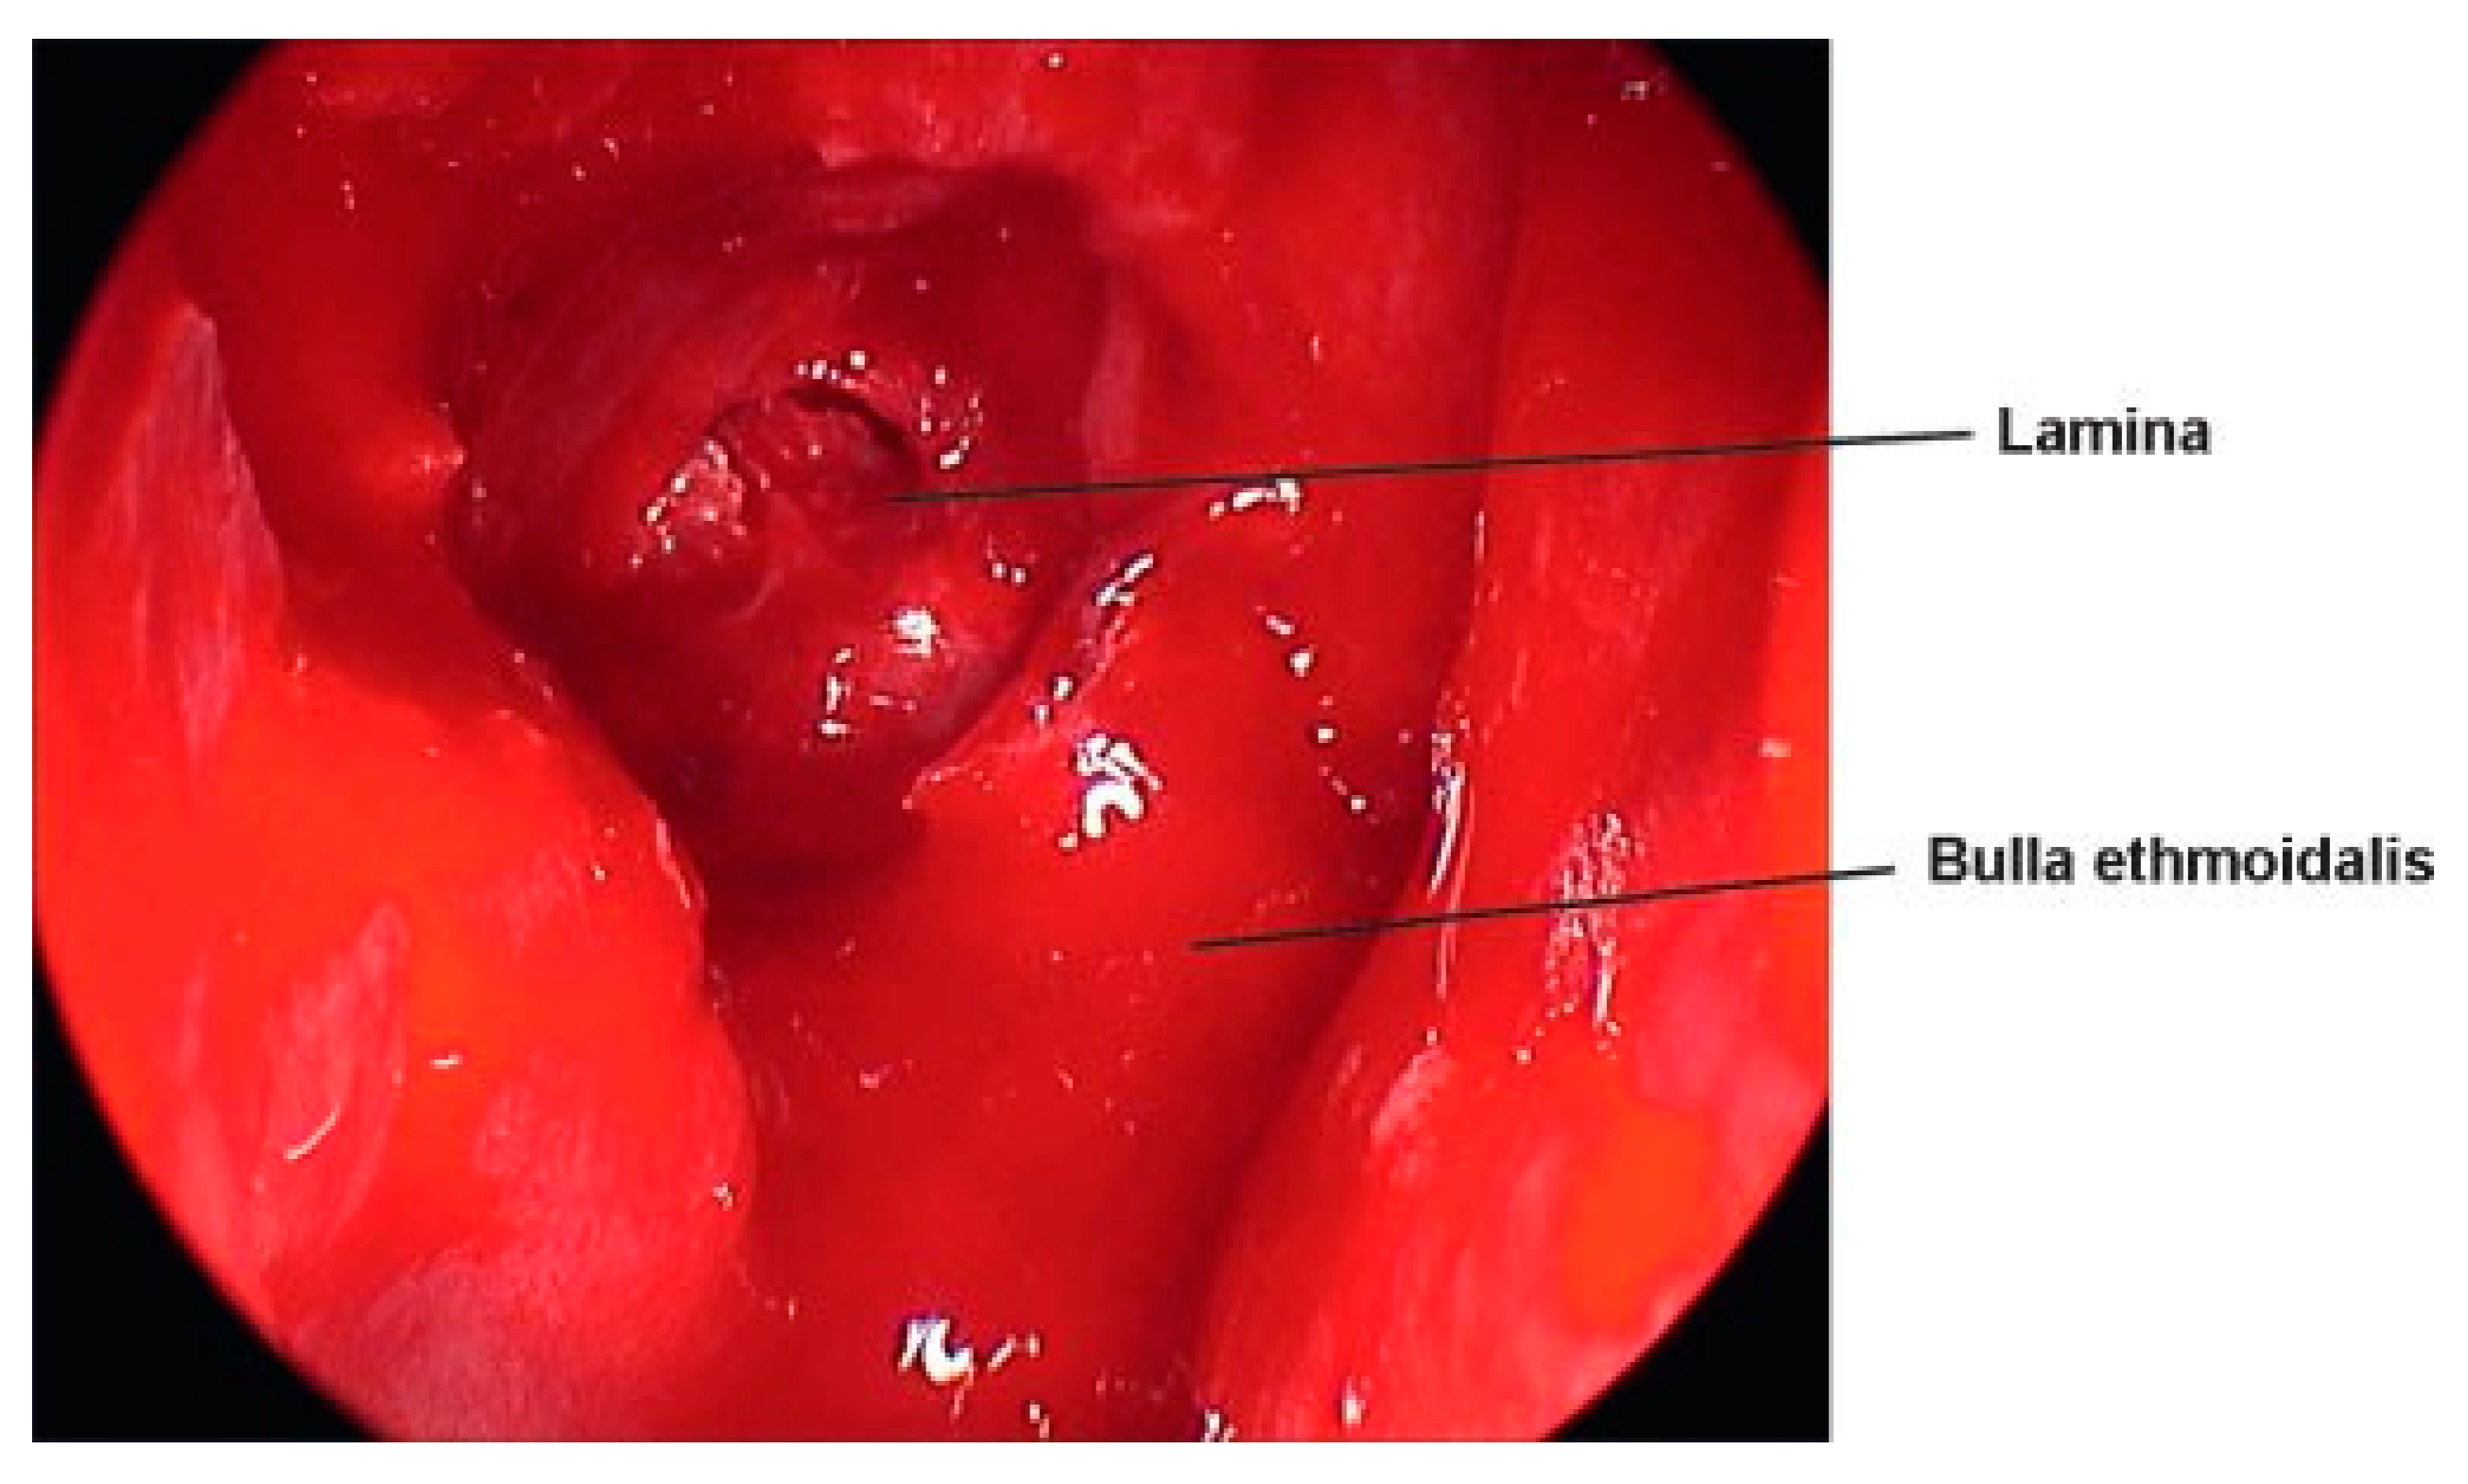

Medial orbital fractures are treated similarly to floor fractures except that these require more extensive knowledge of intranasal anatomy. To undertake the endoscopic repair, you must be aware of endoscopic skull base anatomy and be comfortable taking or medializing the middle turbinate and taking the uncinate process and ethmoid bulla down (Figure 8). If you can do this, you can have a full view of the lamina papyracea (Figure 9). Once the lamina is identified, you can ballot and find the defect. This is then most easily repaired with a Silastic sheet of sufficient stiffness to prevent herniation of the orbital contents. A thin Medpor sheet may also be used (Figure 10).

Figure 8. Medial wall fractures are essentially an extended ethmoidectomy and placement of a Silastic sheet. This is a view of the septum to the left, inferior turbinate takeoff below, and the middle turbinate to the middle of the screen.

Figure 9. Uncinate to the left upfront, bulla taken down, and the anterior ethmoid exposed.